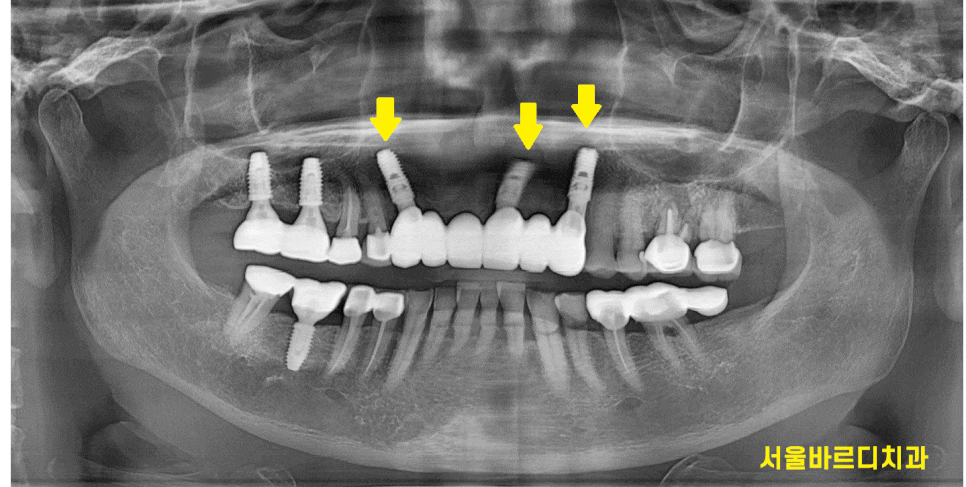

240306

아래 앞니는 자연치아이고

위에 치아 6개를 보철하신 상태네요~

송곳니부터 송곳니까지요.

왼쪽 송곳니 치아 치근 우식이 관찰됩니다.

뿌리쪽 부분이 많이 썩어

치아가 끊겨진것처럼 보이실겁니다.